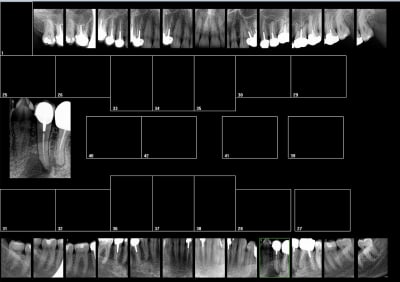

Tiens status meilleur rapport qualité - prix capteur taille 2 isensor woodpecker 1500 balles camera MD960 150 balles. Qui dit mieux ?

sinon avec le film chez les jeunes tu peux faire ca, pour le depistage des caries: